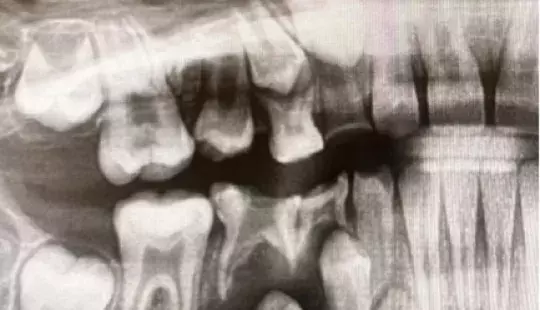

Рентген зубов